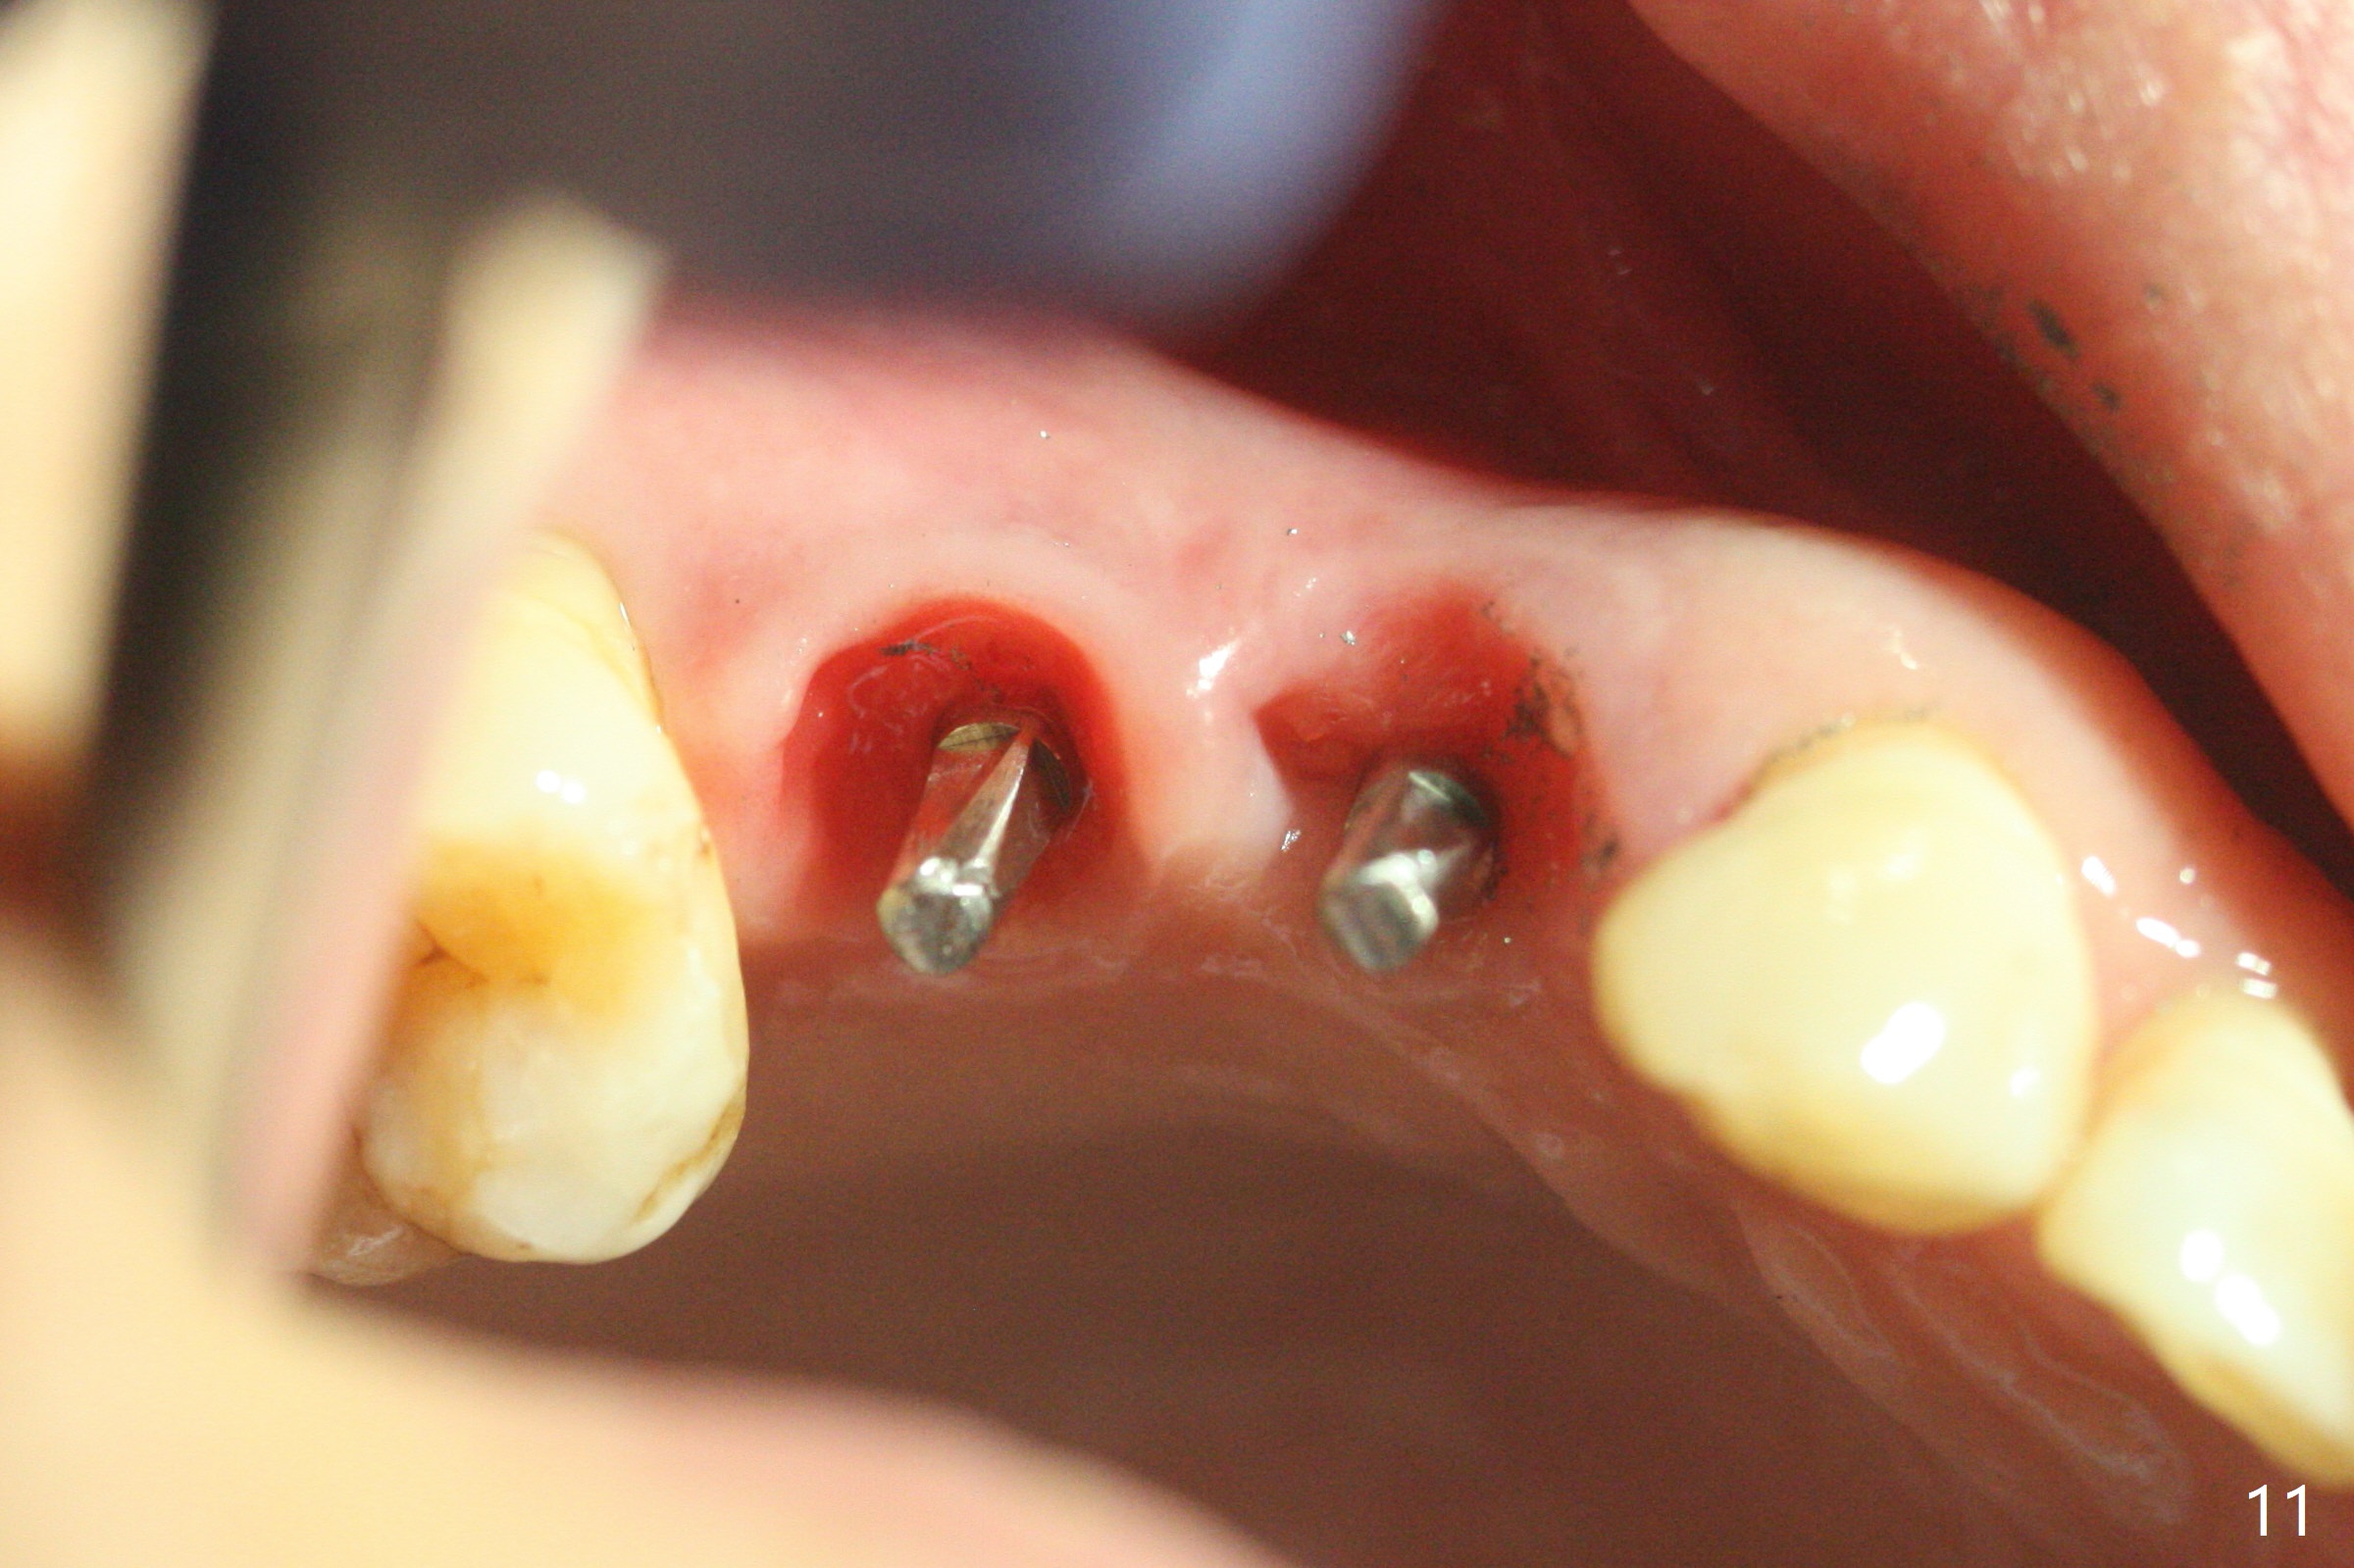

术前CT显示右上4牙槽骨比5窄(图一,二),3.5毫米植体比较合适,况且牙龈厚,基台长的一段式植体显得得当。为了取得最好的植体方位,4先拔除(图三),种植(图四),调整后者深度后,拔除5(术前征求病人同意),开始钻洞(图五),完成种植(图六)。粘性骨粉不仅放置于植体周围,而且6牙根近中(图七),4/5牙槽嵴和龈乳头(P)之间,减少术后龈乳头萎缩(图八:*)。制作两个分开临时牙冠,有利于维持龈乳头。对于病人来说,临时牙冠帮助咀嚼,而对侧拔牙创无法吃饭。术后3个月两个分开临时牙冠(其中一个龈方移位(图九:箭头)保持龈乳头(*)和牙龈外形(图十:*)。临时牙冠取出后,调整基台高度,少量钛屑(不妨大局)附着在健康的牙龈沟(图十一),再次显示两个基台之间龈乳头(图十二:*),衬里,修整的临时牙冠又插回牙龈沟(图十三:箭头),继续维持软组织形态,准备一个月后,调整基台边缘(图十二:箭头),取模。术后五个月大部分骨粉依然保留在植体和邻牙周围,龈乳头退缩不多(图十四: P)。三个月后(术后六个月)钛削无影无踪(图十五,与图十一对比))。永久性牙冠周围空间慢慢会消失(图十六,使用临时性胶水)。